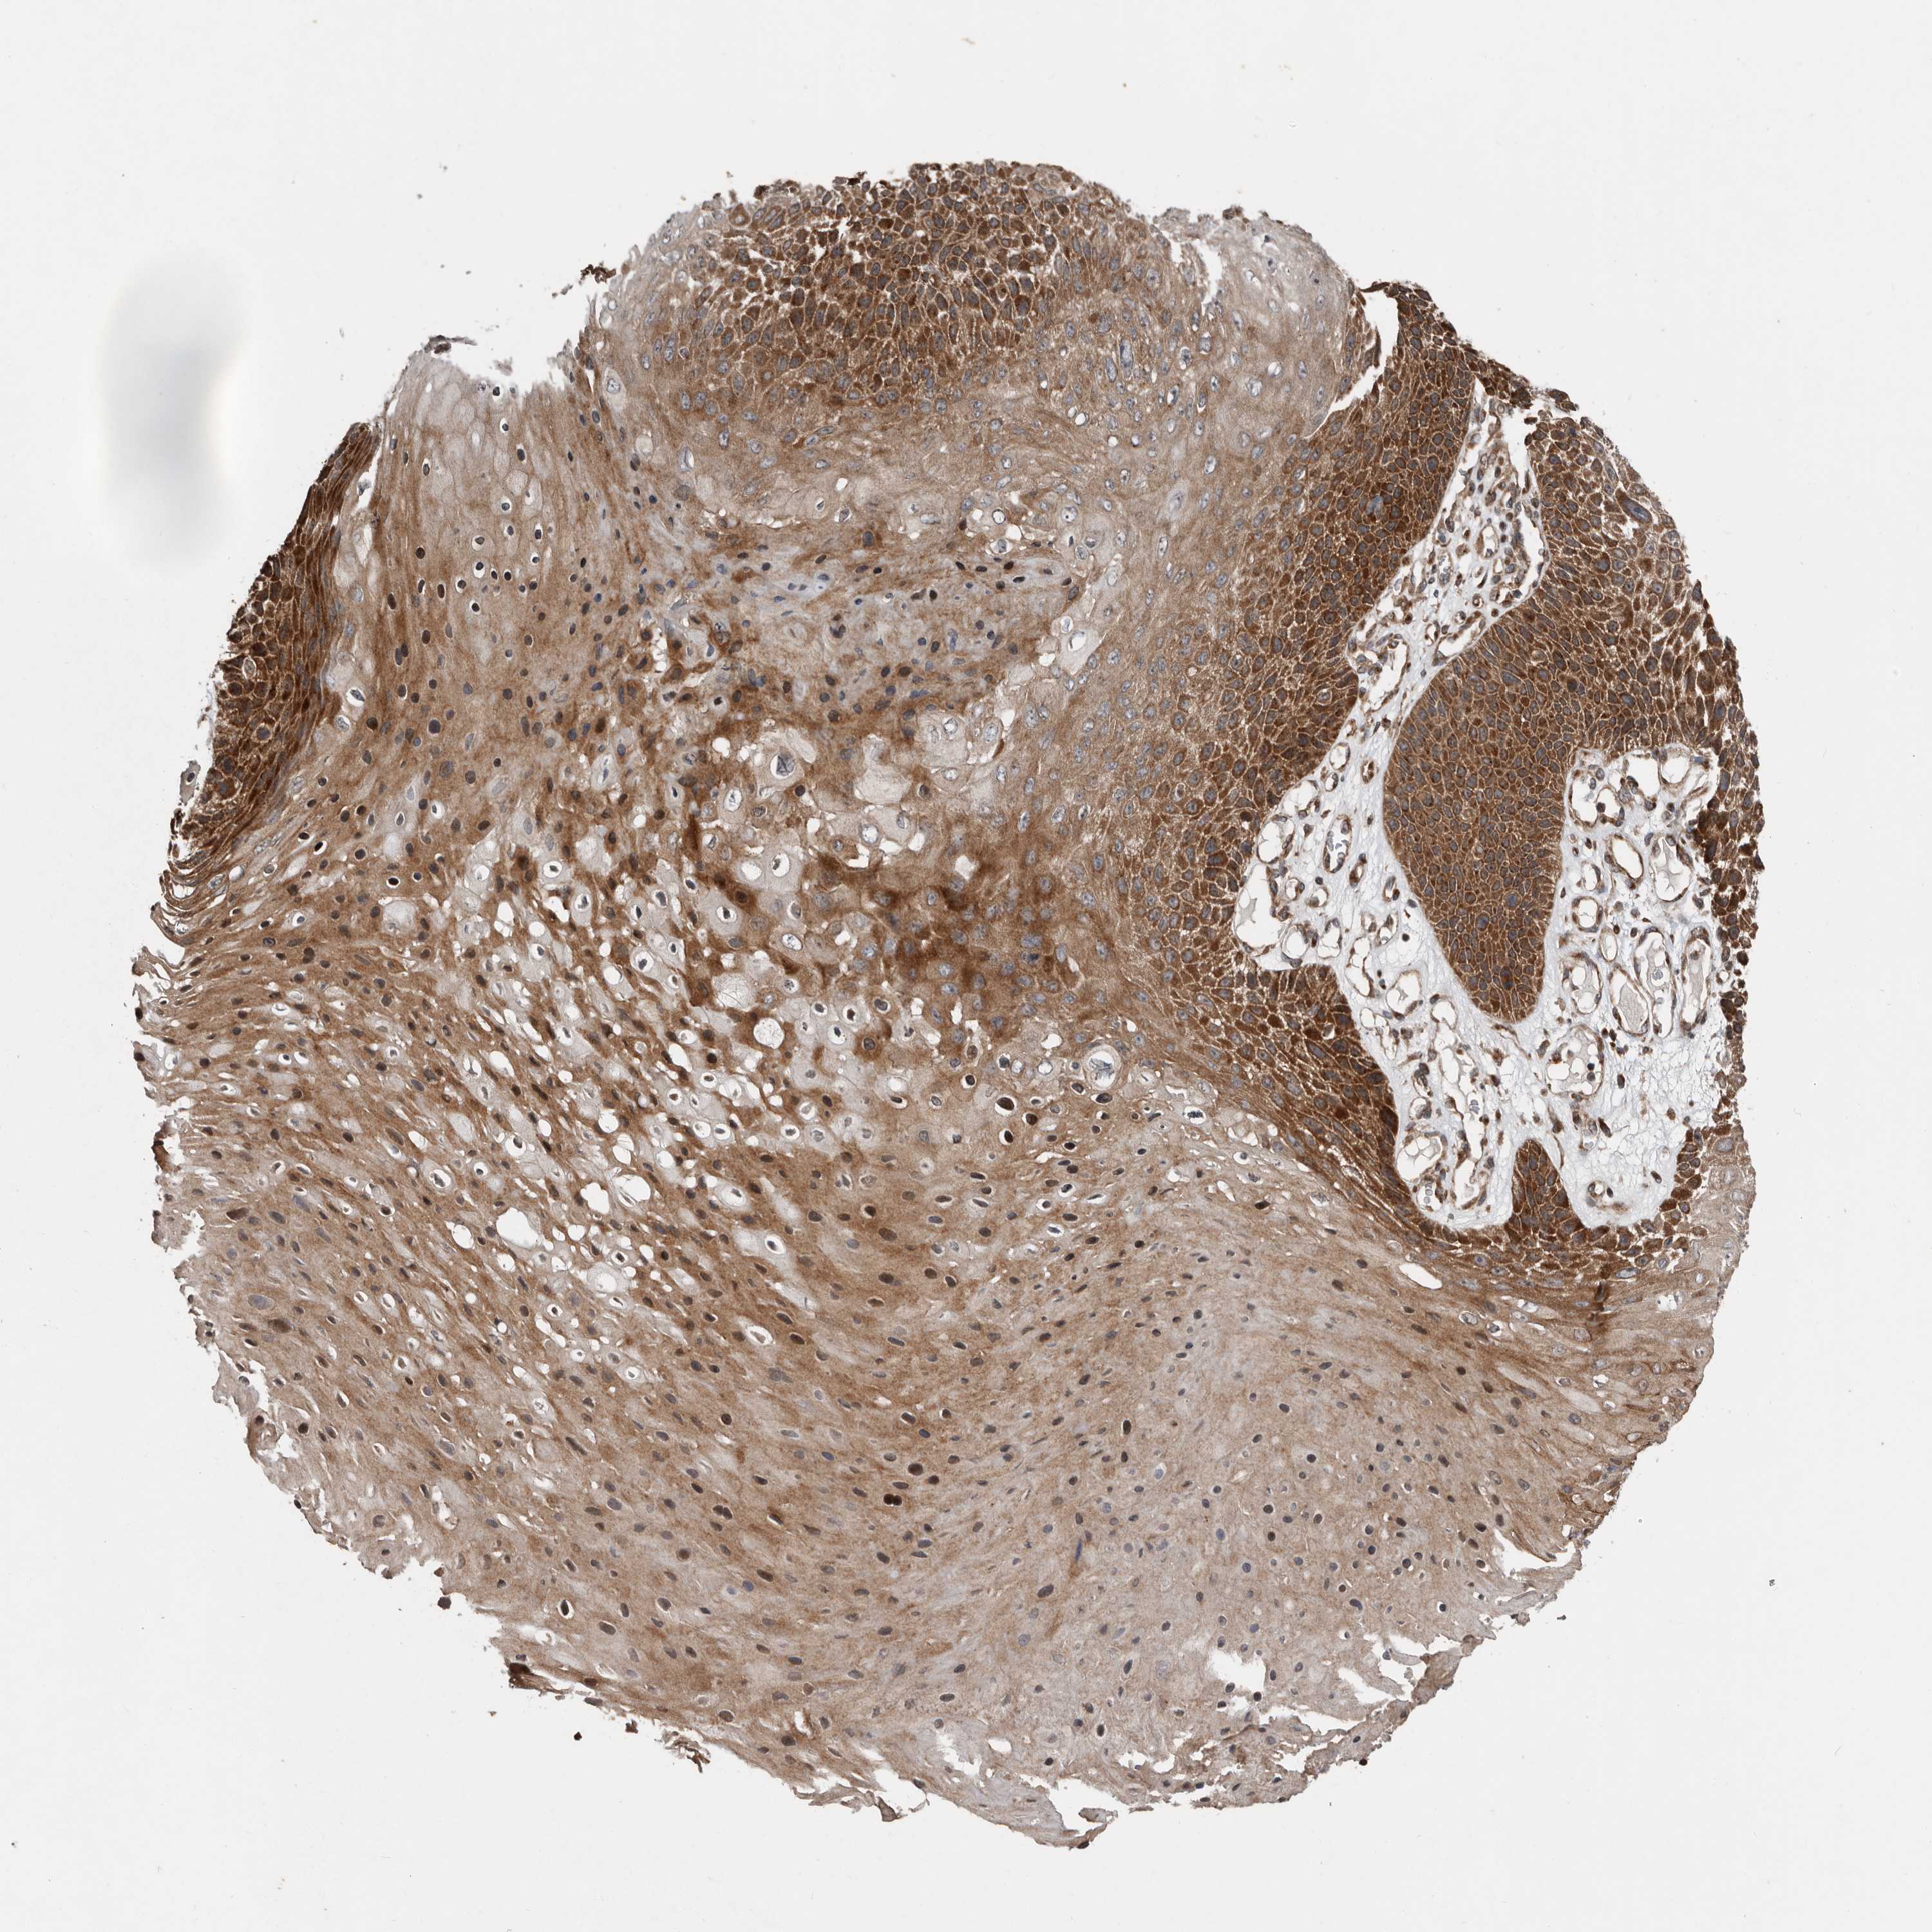

SKIN CANCER - Protein expressioni

A mouse-over function shows sample information and annotation data. Click on an image to view it in a full screen mode. Samples can be filtered based on level of antibody staining by selecting one or several of the following categories: high, medium, low and not detected. The assay and annotation is described here.

Each image is clickable and will lead to virtual microscopy that enables deeper exploration of all samples and also displays staining intensity scores, fraction scores and subcellular localization as well as patient and tissue information for each sample.

Antibody HPA028579

Staining

High

Medium

Low

Not detected

Intensity

Strong

Moderate

Weak

Negative

Quantity

>75%

75%-25%

<25%

None

Location

Nuclear

Cytoplasmic/membranous

Cytoplasmic/membranous,nuclear

Basal cell carcinoma